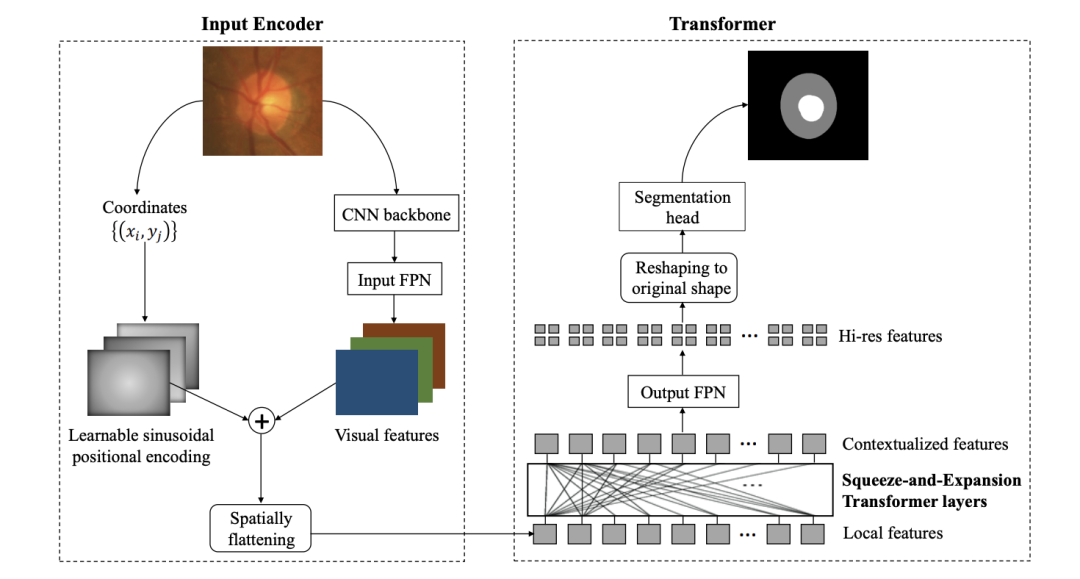

《Medical Image Segmentation Using Squeeze-and-Expansion Transformers》